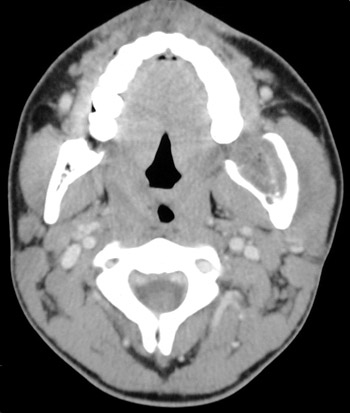

![]() | This head CT scan in "soft tissue window" demonstrates a mass lesion expanding the ramus of the left mandible of a teenage male. This is an ameloblastoma. The histologic pattern mimics the enamel organ of the tooth. Neoplasms of a related histologic appearance include craniopharyngiomas of the sella turcica and adamantinomas of long bone. |